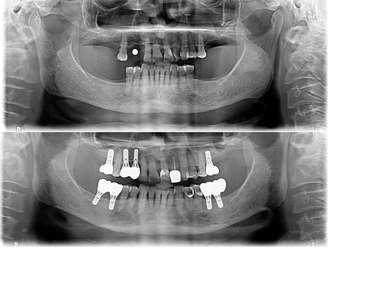

Complex cases benefit from our carefully orchestrated staging protocol. We prioritize healing, integration, and optimal prosthetic outcomes through a methodical approach that has been refined over thousands of cases.

When possible, we employ advanced minimally invasive protocols that reduce surgical trauma, accelerate healing, and improve patient comfort. Our techniques often eliminate the need for extensive incisions or prolonged recovery periods.